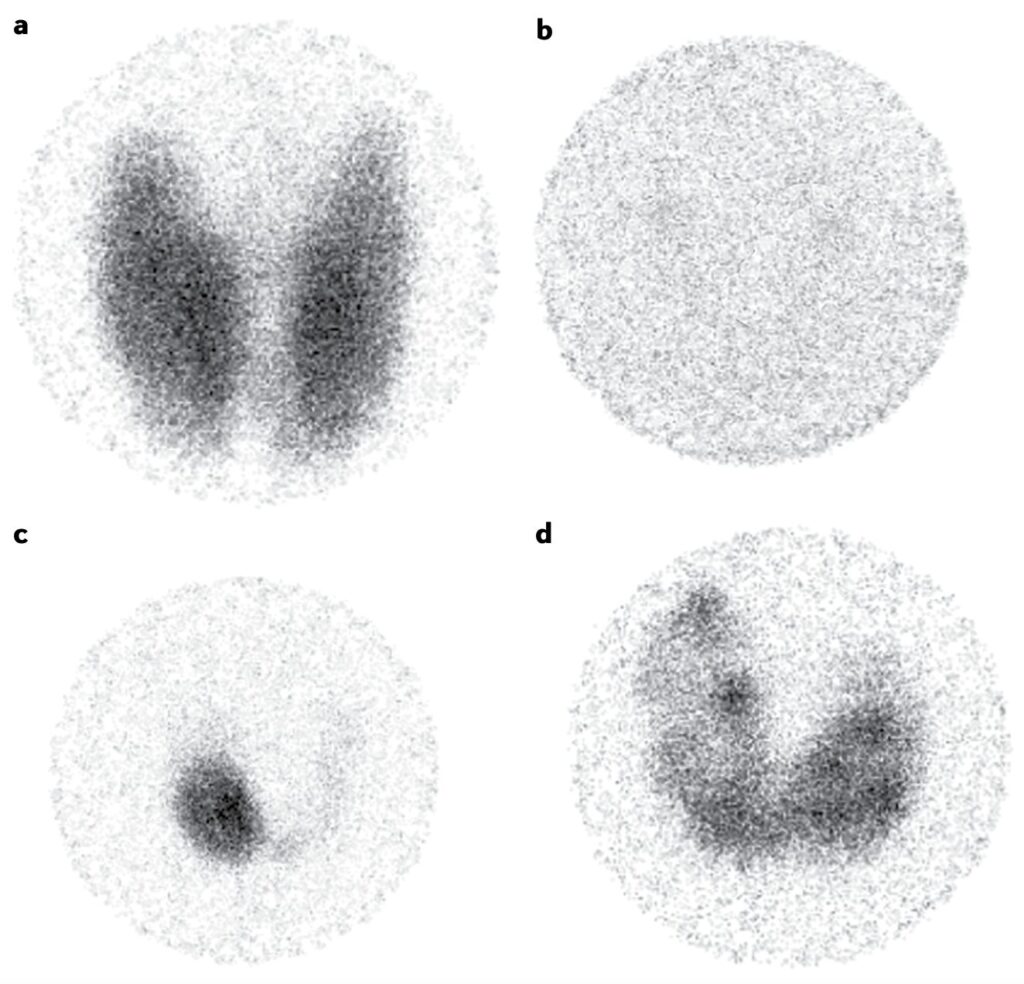

様々な甲状腺機能亢進症における甲状腺シンチグラフィーの画像の例です2)。

a:バセドウ病における典型的な所見であり、両側性の肥大した甲状腺における同位体のびまん性で強い集積が含まれます。

b:無痛性甲状腺炎による破壊性甲状腺中毒症の1例であり、甲状腺は描出されません。

c:中毒性腺腫の例であり、自律的に機能している結節はアイソトープを蓄積します。結節からの過剰な甲状腺ホルモン産生により甲状腺刺激ホルモンが抑制されているため、甲状腺外組織での取り込みは観察されません。

d:中毒性多結節性甲状腺腫の場合、アイソトープが甲状腺全体のいくつかの結節領域に集中しています。